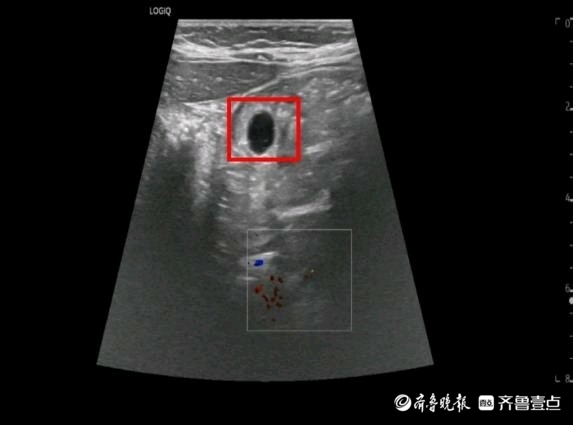

据家长描述,“水宝宝”在误服时仅有黄豆大小,可其遇水膨胀的特性让情况变得十分紧急。儿科医生王福建接诊后,第一时间联系B超室进行检查,B超室医生苏珊迅速到位,即刻为患儿开展胃肠超声检查。结果显示,仅在误服1小时后,水宝宝已在胃内膨胀至1.2x1.0cm,大小堪比玻璃球。若继续膨胀,其直径很可能超过孩子食管宽度,不仅无法通过胃镜取出,还易造成胃肠梗阻,到时候只能开刀手术!情况刻不容缓!